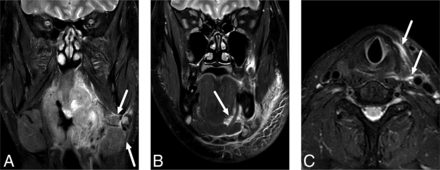

SMS edema was the most common (92%), followed by VS (72%) and SLS (24%) edema (Fig 4). The SMS and SLS edema patterns were not significantly differently distributed among the abscess locations, whereas VS edemas were most common in inferiorly located abscesses (42% versus 33% and 25% in superior and widespread types, P = .001). The patients with VS edemas had larger abscesses (3.8 versus 1.5 mL, P < .001) and higher CRP (142 versus 90, P = .005) than those without. Similarly, the patients with SLS edemas had larger abscesses (4.6 versus 2.7 mL, P = .047). In the interobserver analysis, these edema patterns had moderate-to-substantial agreement (93%, 85%, and 78% agreement, and κ = 0.47, 0.64, and 0.52 for SMS, VS, and SLS, respectively).

Examples of SMS (A), SLS (B), and VS (C) edema patterns on fat-suppressed T2-weighted Dixon images. Arrows indicate edema.